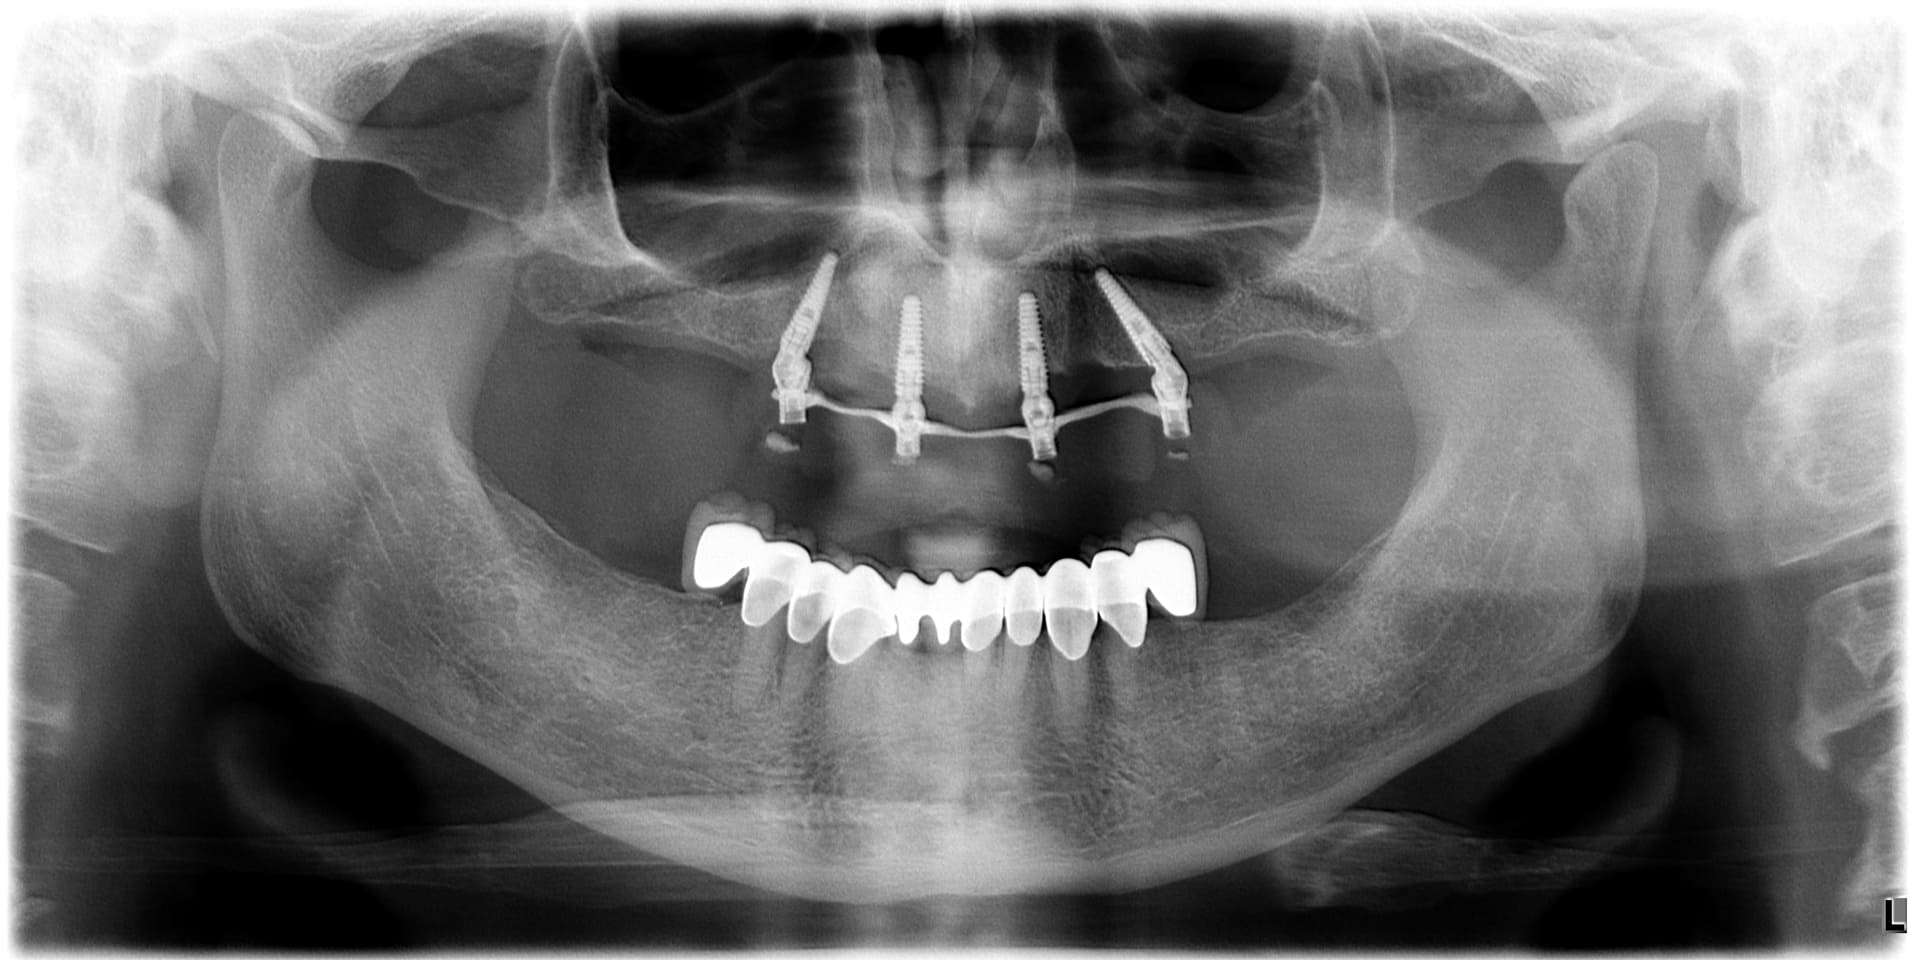

Paziente 2

< Prima

Dopo >